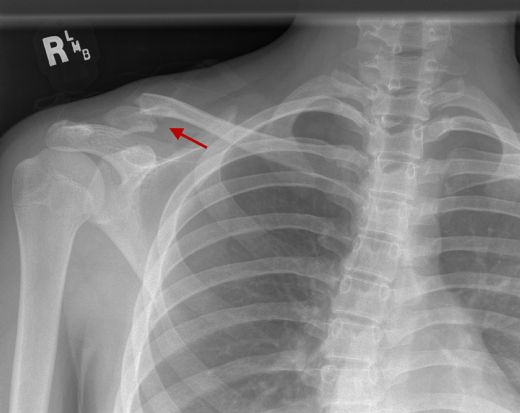

Omuz Kemikleri Özellikleri